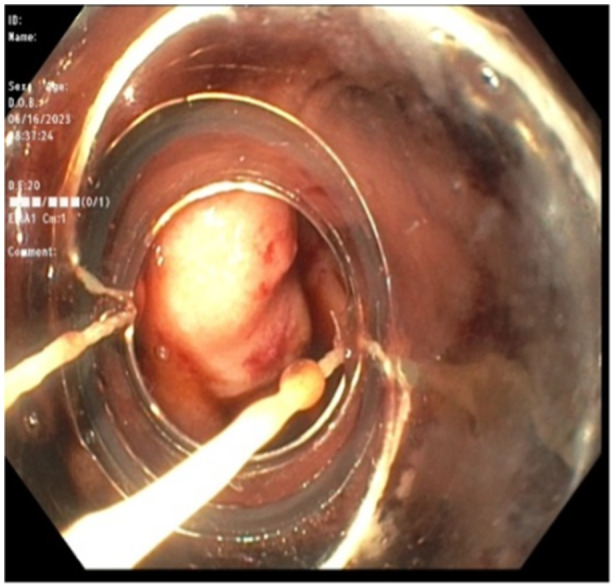

Ectopic varices are defined as portosystemic venous collaterals occurring in the gastrointestinal tract outside of the cardio-esophageal region. Duodenal varices are not routinely encountered by pediatric gastroenterologists. At the time of this case report, there are no consensus guidelines on the management of bleeding duodenal varices in pediatric patients. This is a case of a 14-year-old young woman with a history of multi-visceral transplantation due to short gut syndrome. The patient had developed duodenal varices near her transplant anastomosis, which were incidentally biopsied on endoscopy causing resultant bleeding that required endoscopic hemostasis. This case highlights the need for recognition of duodenal varices as a potential etiology of gastrointestinal bleeding in children and describes band ligation as an effective hemostatic modality.

Abstract Image